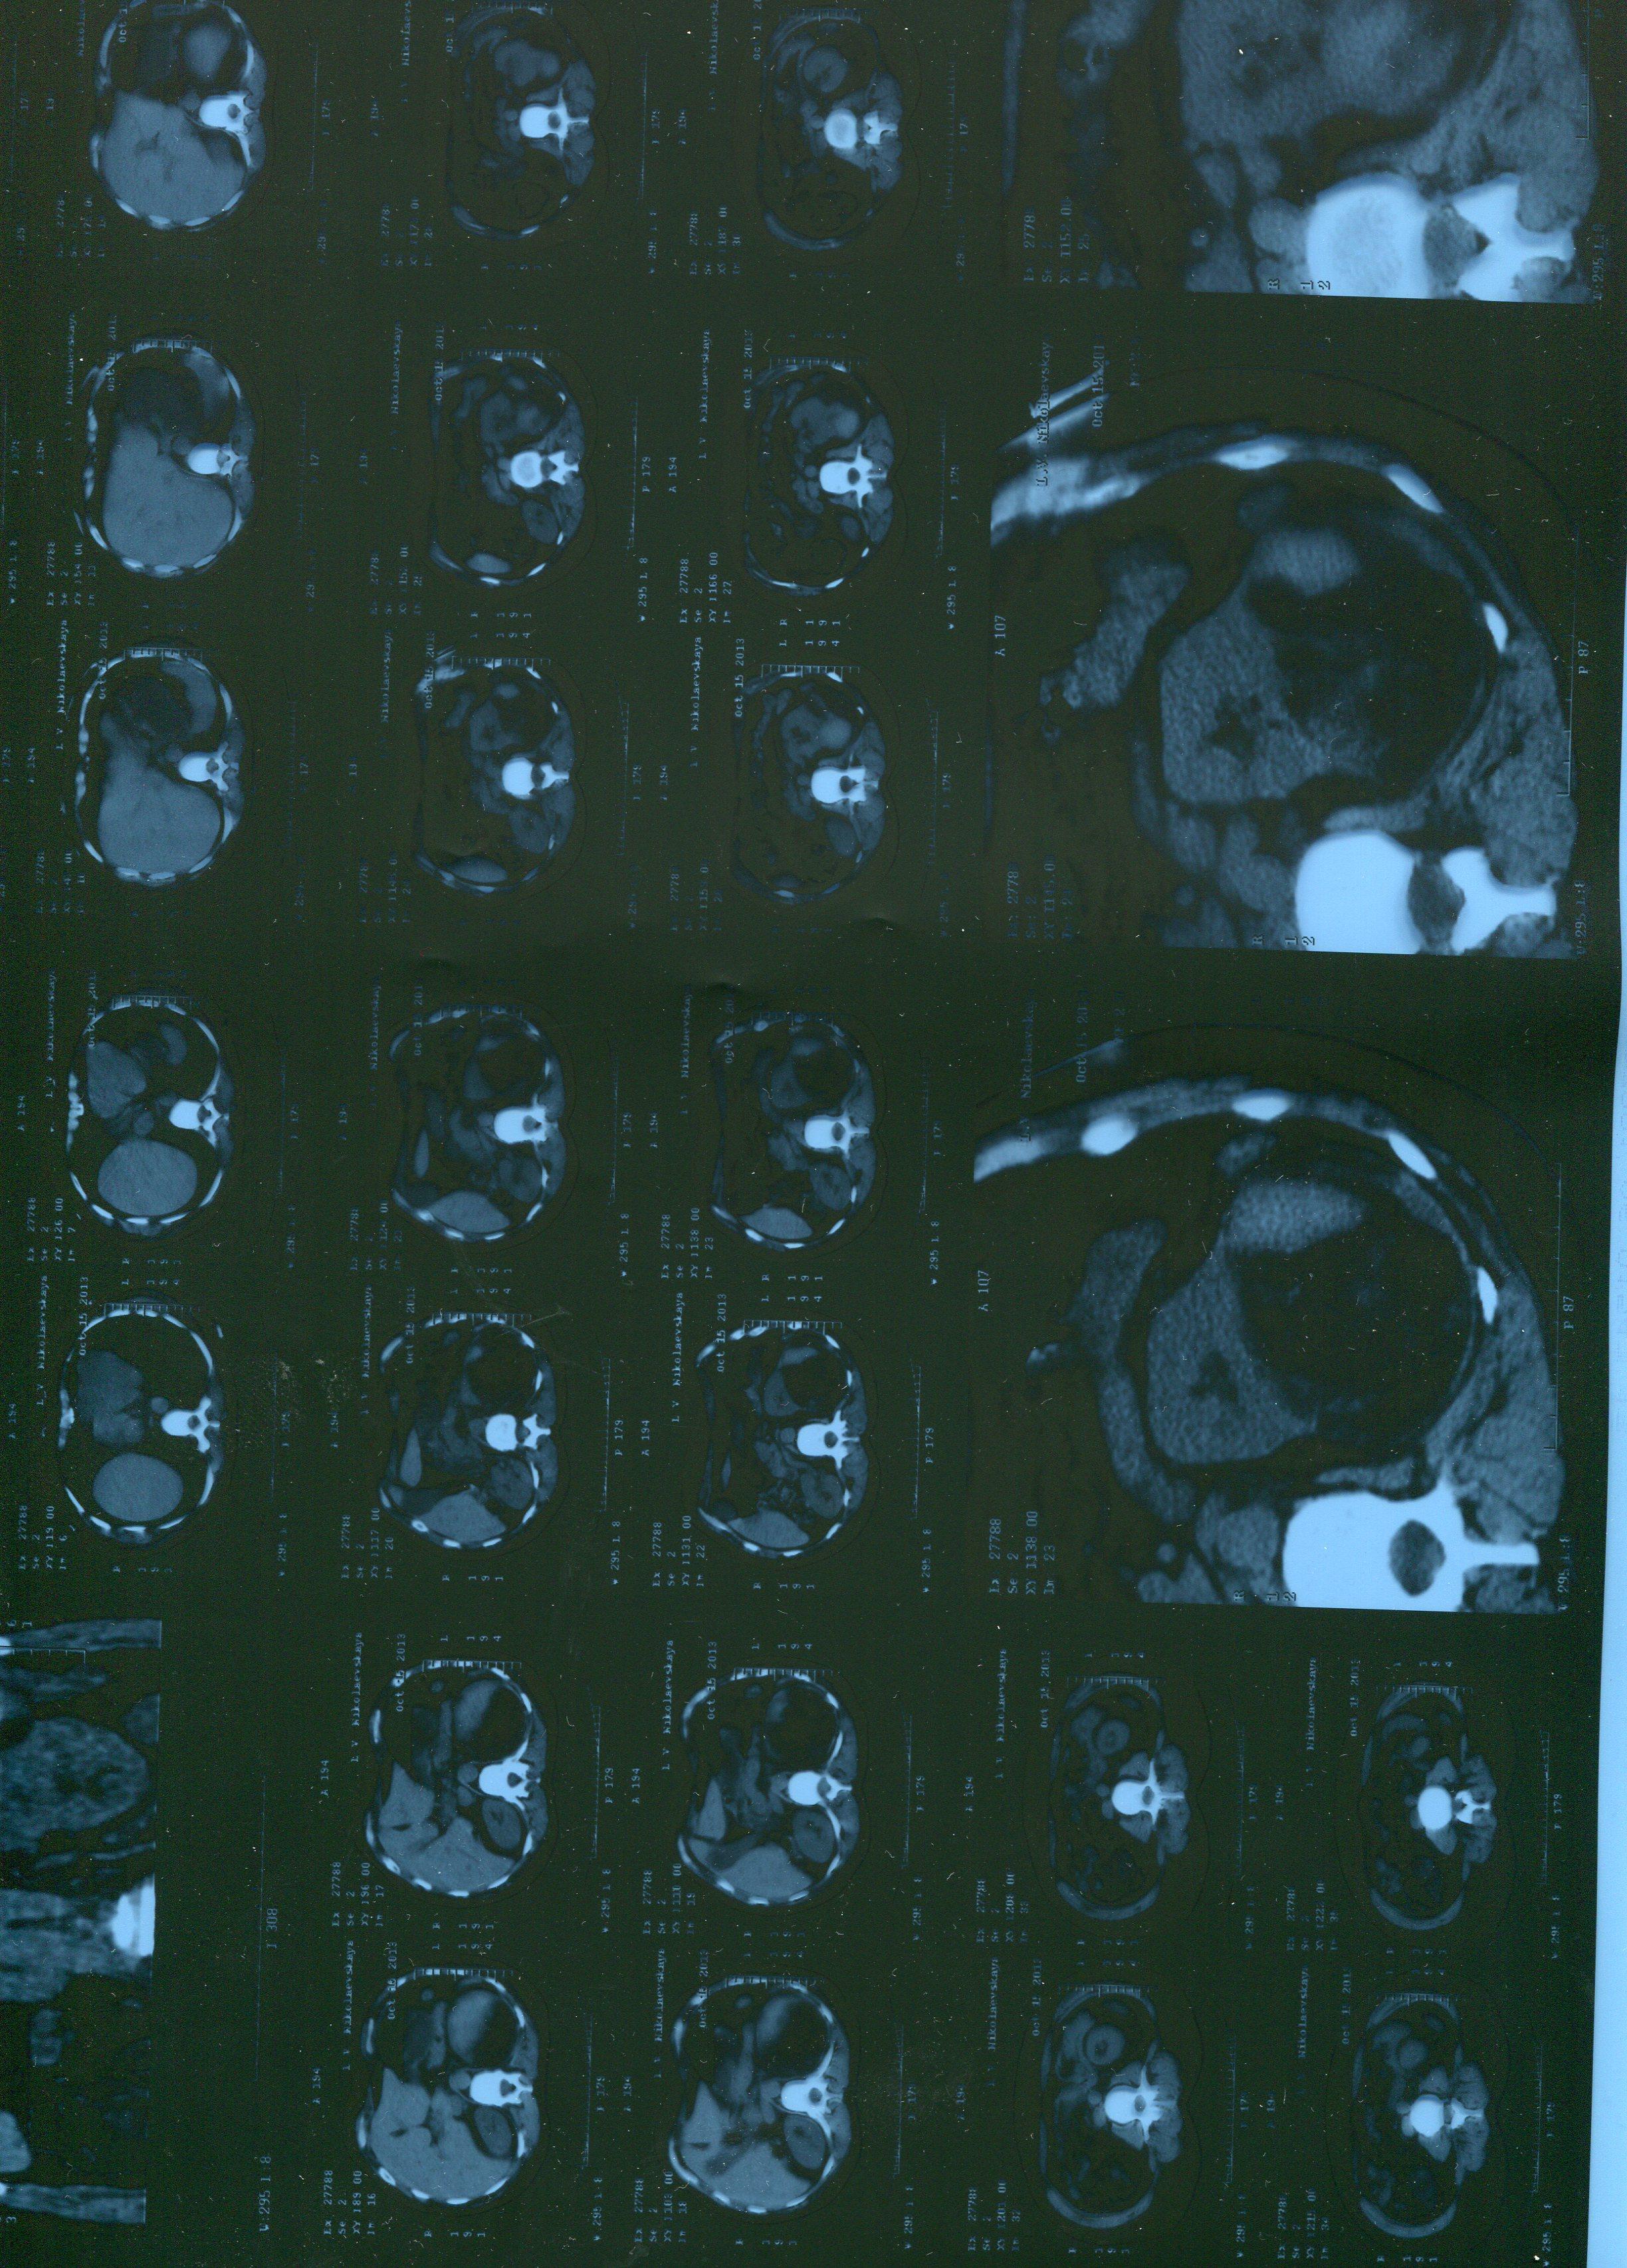

можно по снимку томографии определить какая это опухоль?

Случайно обнаружили опухоль почки. Обследовалась по другому поводу? Жду плановой госпитализации. Что вы можете сказать по снимкам? можно ли сохранить почку?

Обычно проводится дополнительное обследование: например, УЗИ. Ваш снимок проводился без дополнительного контрастирования, что затрудняет прямой ответ ан поставленный вопрос. Доверьтесь врачам, вопрос будет решен в период госпитализации, на дооперационном этапе.